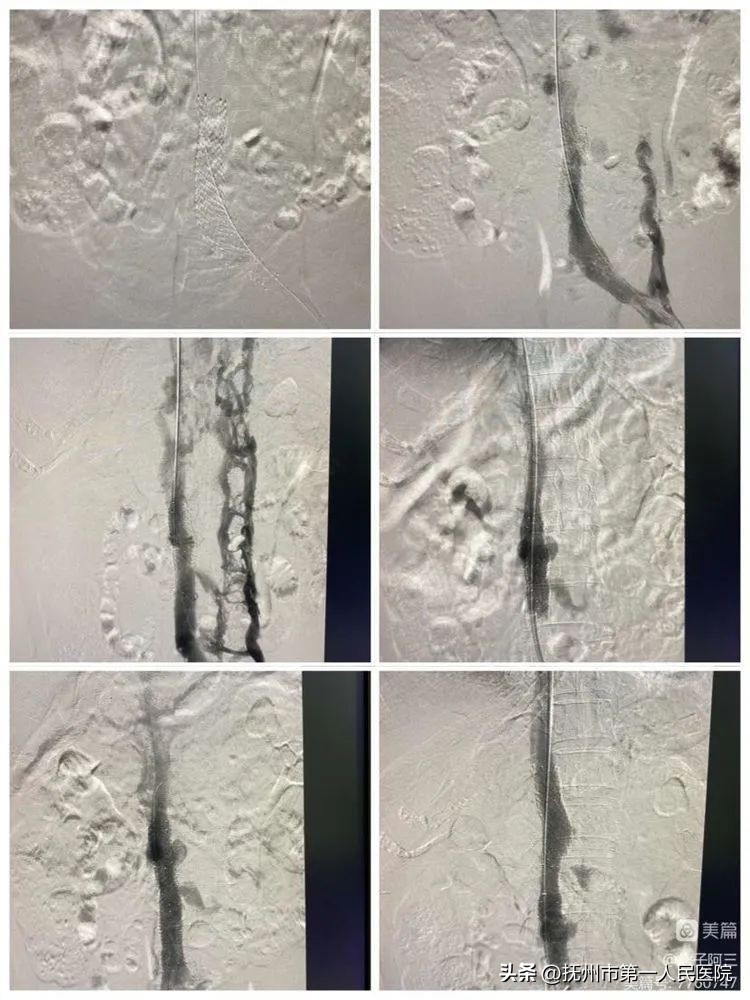

下腔静脉开通后给予下腔静脉球囊(F8—F14)逐渐扩张成型

下腔静脉球囊(F8—F14)逐渐扩张成型结束后立马造影、发现下腔静脉通畅

10分钟后再次造影发现、下腔静脉回缩再次狭窄、患者下腔静脉长段闭塞狭窄遂行下腔静脉支架植入

支架植入术中造影

并给予F14球囊内扩